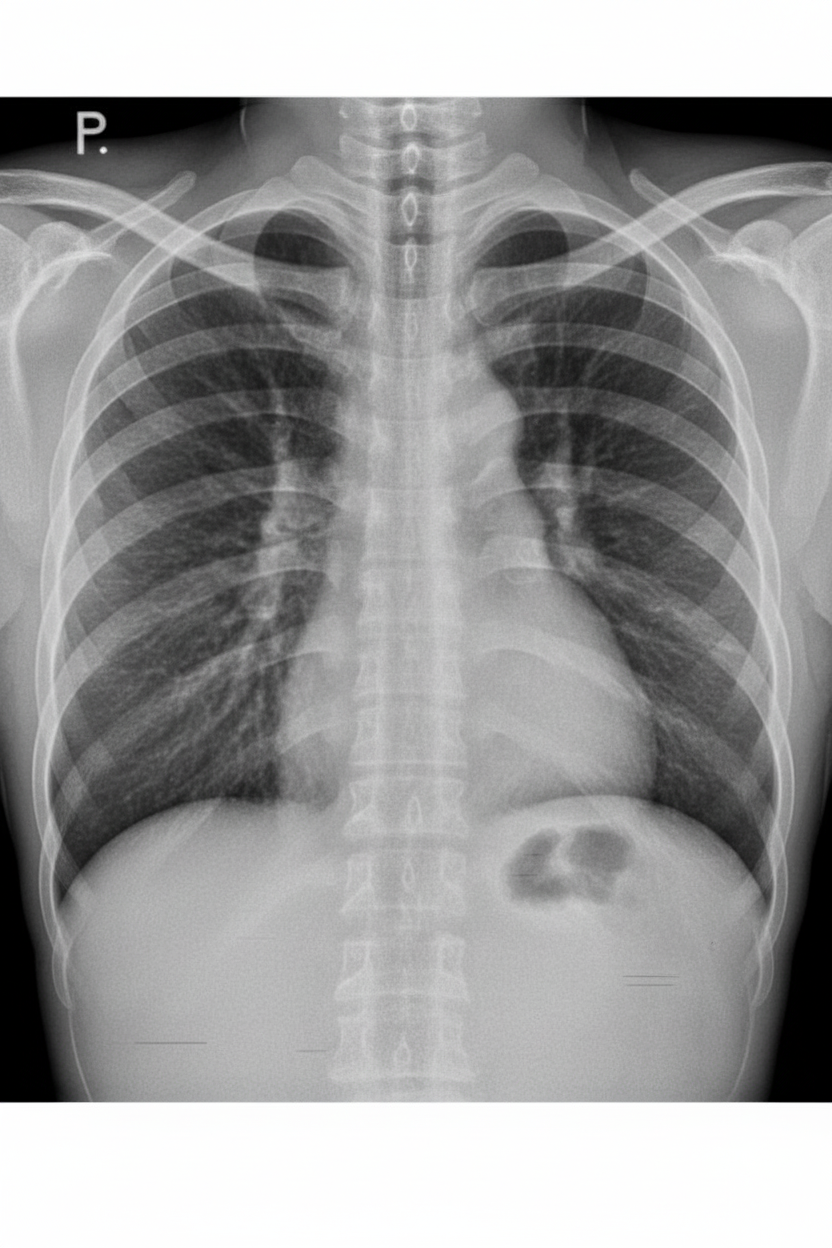

Explanation: ***Furosemide*** - **Loop diuretic** that acts on the **thick ascending limb of Henle** to rapidly promote **natriuresis** and **diuresis**, effectively reducing **preload** in acute pulmonary edema. - First-line treatment for **acute heart failure** with pulmonary edema due to its **rapid onset** and powerful fluid removal capacity. *Thiazide* - **Thiazide diuretics** are less potent and have a **slower onset** of action, making them unsuitable for acute pulmonary edema emergencies. - Primarily used for **chronic hypertension** and **mild heart failure**, not for rapid fluid overload management. *Acetazolamide* - **Carbonic anhydrase inhibitor** with weak diuretic effect, primarily used for **glaucoma**, **altitude sickness**, and **metabolic alkalosis**. - Ineffective for managing **acute fluid overload** due to its limited natriuretic capacity and potential to cause **metabolic acidosis**. *Neomycin* - **Aminoglycoside antibiotic** with no diuretic properties, used to reduce **ammonia-producing bacteria** in hepatic encephalopathy. - Completely unrelated to **fluid management** and would be contraindicated due to potential **nephrotoxicity** in heart failure patients.